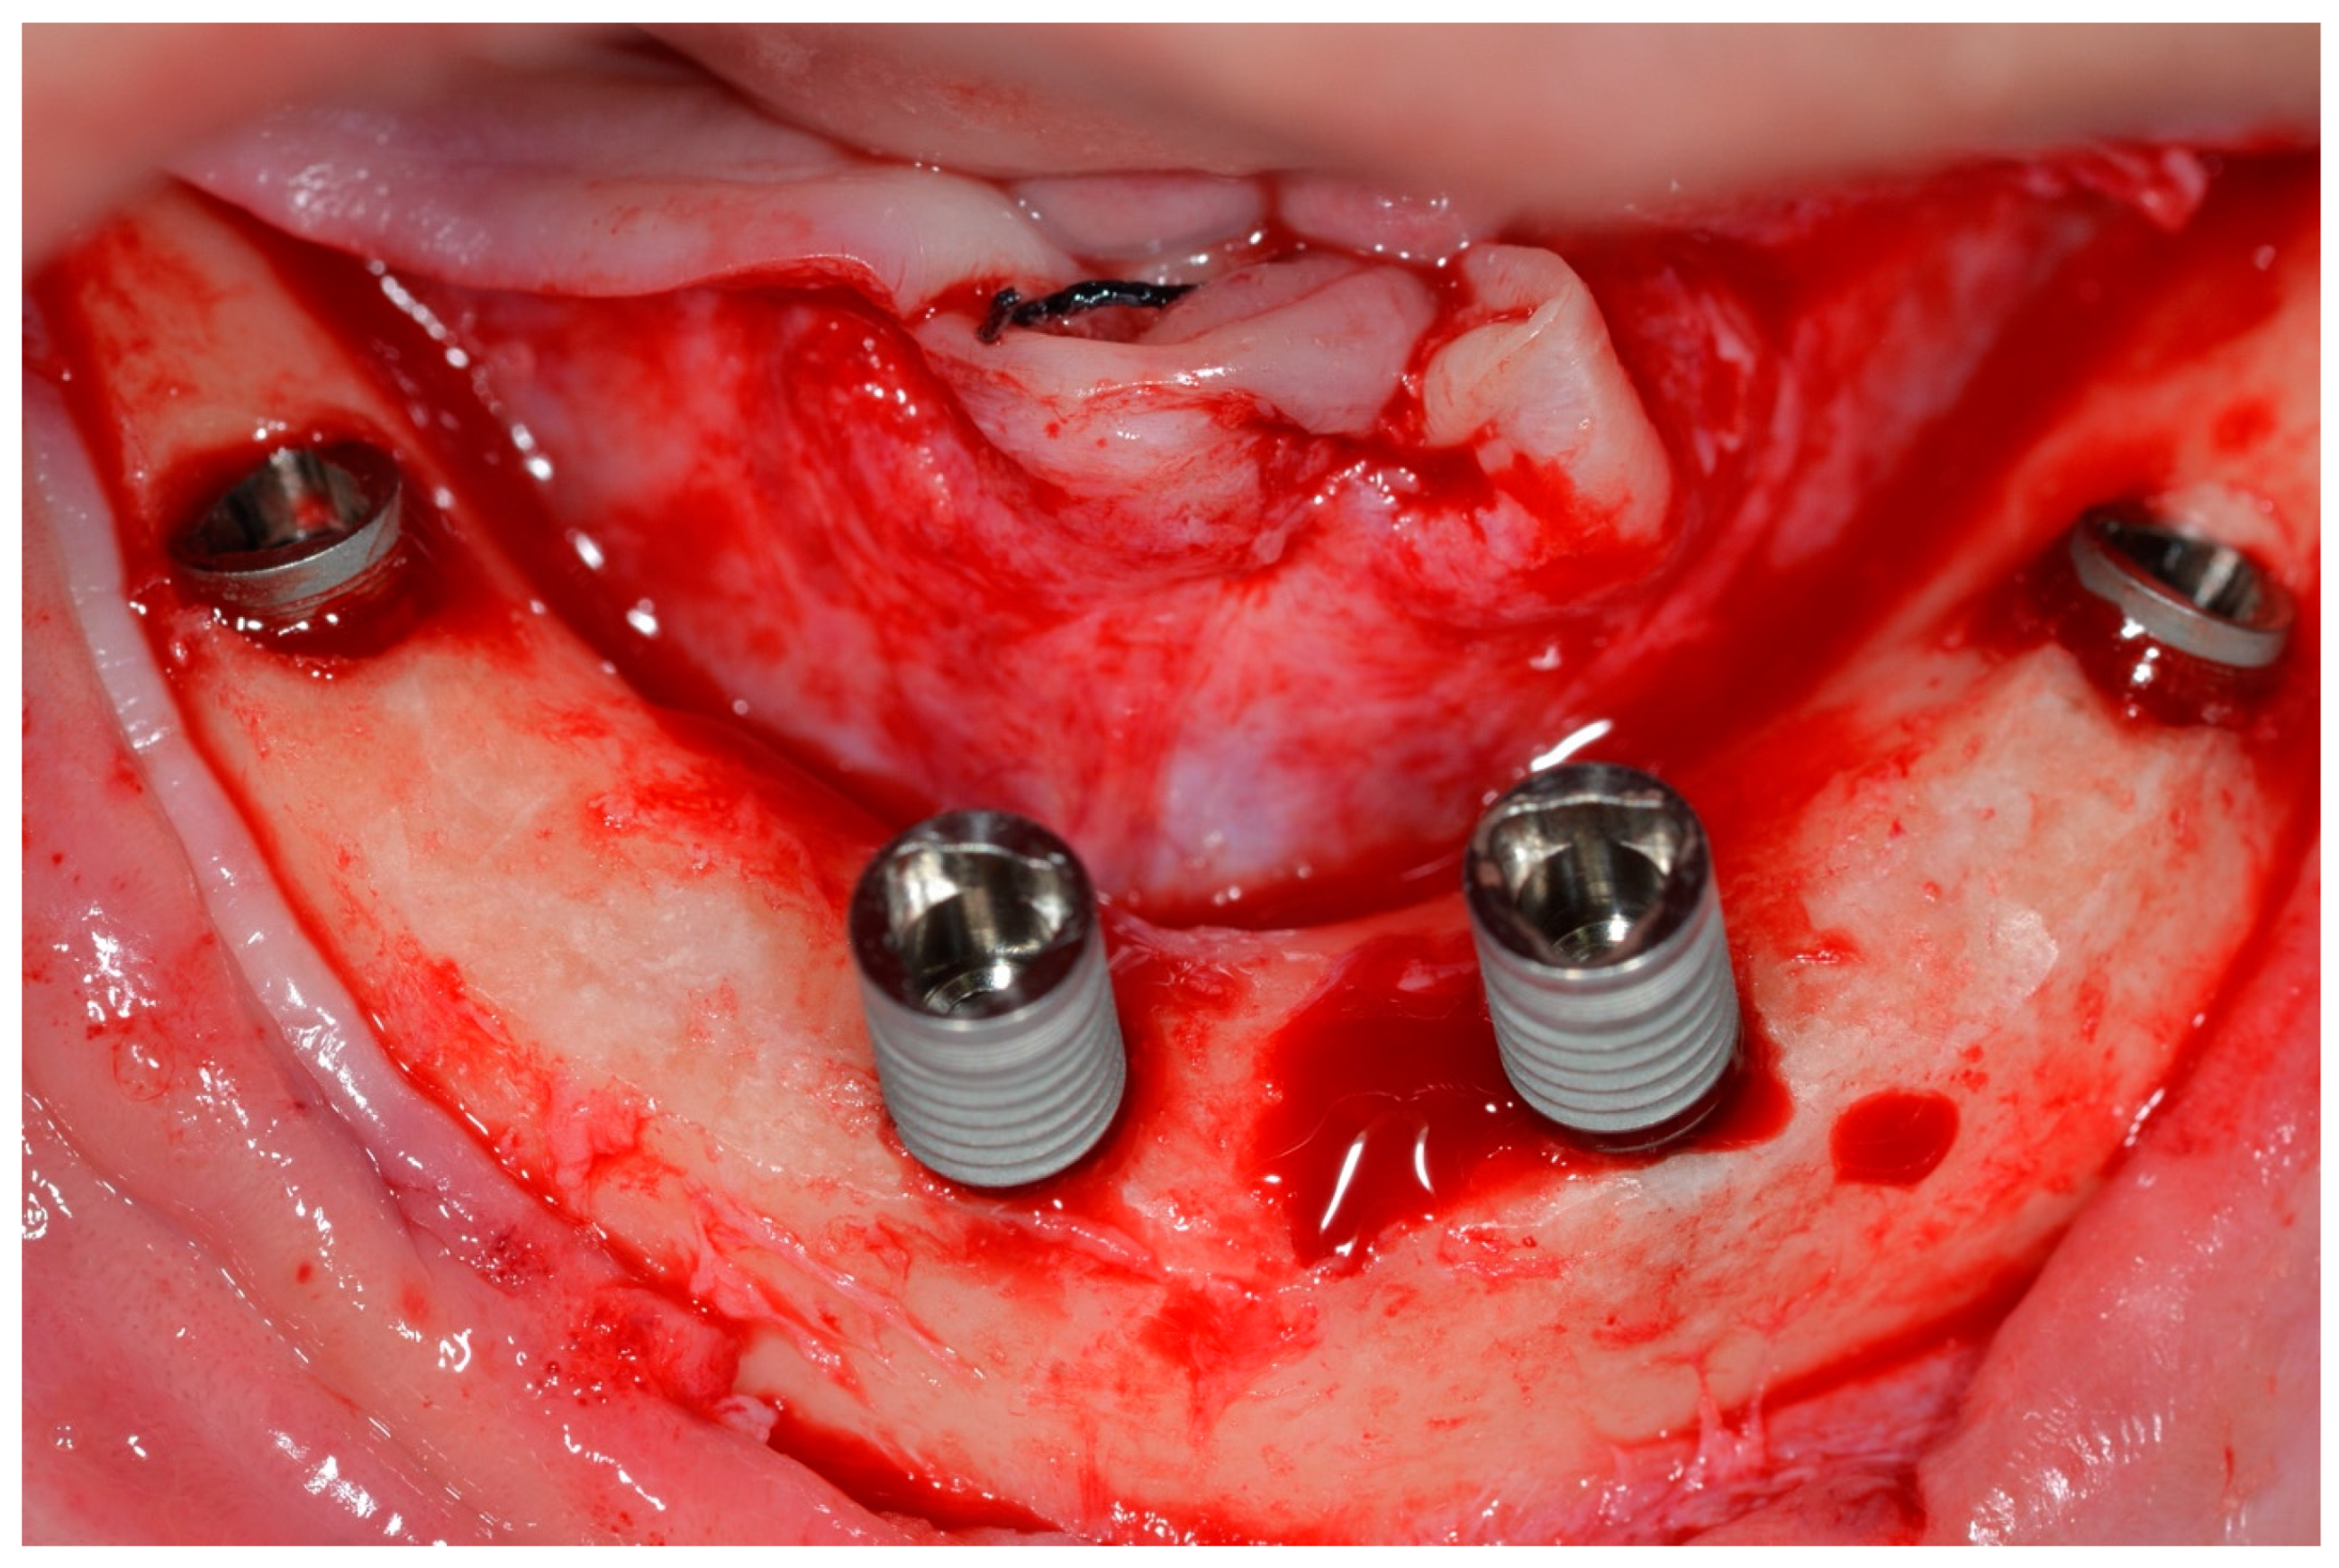

During bone instrumentation, when the surgeon’s experience enabled them to sense that the implant sites would have poor bone density, they performed sub-instrumentation to obtain the highest torque value possible at every site [10]. The surgeons decided this based on their extensive experience with All-on-Four treatments to promote lateral compression of the bone, thereby increasing primary stability [10]. The implants used in this study were tapered, with a rough surface, internal tri-channel connection implants (TRI Bioneck RP ∅ 4.3 mm, Dérig, São Paulo, Brazil) (Figure 5).

Figure 5.

TRI Bioneck RP implant (Dérig, São Paulo, Brazil).

The implants were initially inserted with the handpiece adjusted to an initial IT of 45 Ncm. When the handpiece was stalled, the implant was manually inserted using a custom-made torque wrench [12]. This instrument allowed torques of up to 200 Ncm (Figure 6) to be measured until the implant was completely seated (Figure 7 and Figure 8).